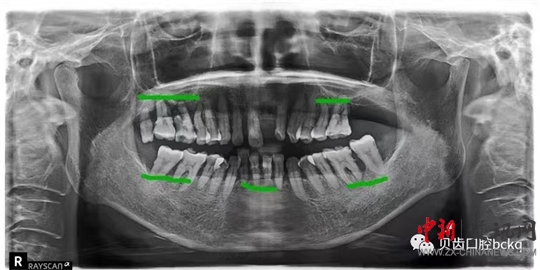

下面這兩張x光片是比較典型的牙周炎的影像資料。該患者的全口所有牙齒都出現(xiàn)了不同程度的松動(dòng)。患者現(xiàn)在感覺無法用牙齒咀嚼。坦白地講,牙周炎發(fā)展到這種程度,很多時(shí)候醫(yī)生也束手無策了。為了保留更多的牙槽骨,醫(yī)生回不得不拔掉哪些嚴(yán)重松動(dòng)的患牙。